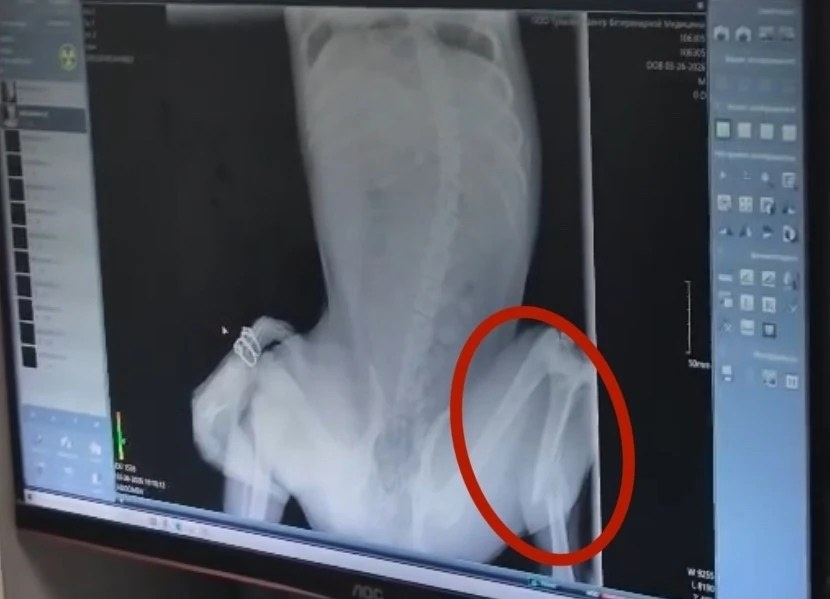

Студенты просят помочь сбитой собаке

Вчера на проспекте Ленина собака попала под колеса автомобиля.

Подобравшие животное студенты привезли его в клинику на улице Болдина. После обследования стало известно, что у собаки перелом лапы – ей требуется операция. Сейчас животное в стационаре.